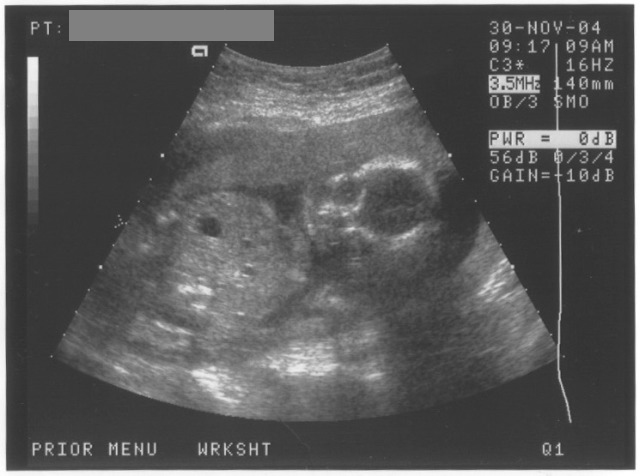

11/30/04